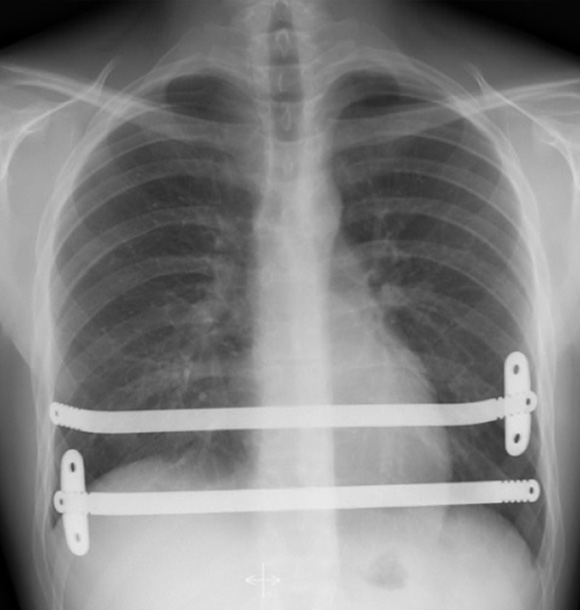

Following the operation (see video) which take anywhere between 1 to 3 hours a chest x-ray is performed to confirm position of the bar and lungs are fully re-inflated.

Post-operative Chest X-ray’s showing a 2-bar technique with one stabiliser on each bar (Left) and 1-bar with two stabilisers (Right). Note significant spinal scoliosis or sideways spinal curvature

After: You will be transferred to the recovery area and a chest x-ray will be performed to confirm the lungs are fully re-expanded. You will be transferred to the ward or the high dependent unit following the surgery. You will be offered a Patient Controlled Analgesia or PCA pain pump following the surgery. This is a drip which allows you to administer painkiller directly in which you can control based on your pain experience.